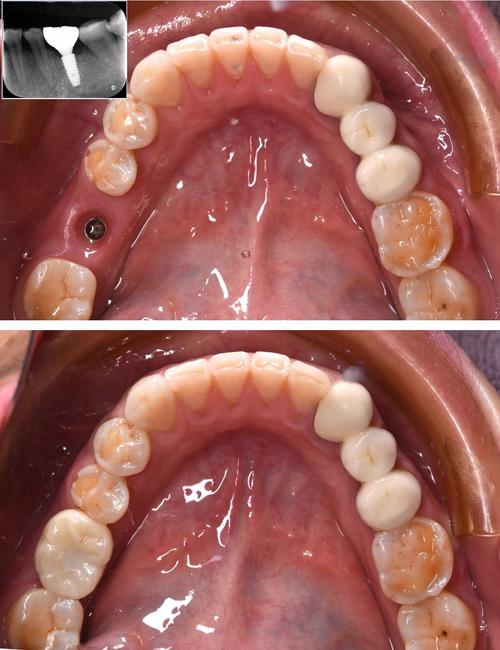

- 种植体植入:在局部麻醉下切开牙龈,逐级备洞后将种植体植入牙槽骨,缝合伤口,术后拍摄X光片确认位置。

- 基台与牙冠安装:骨结合完成后,安装基台,取模制作牙冠(全瓷冠、金属烤瓷冠等),试戴调整后粘固完成。